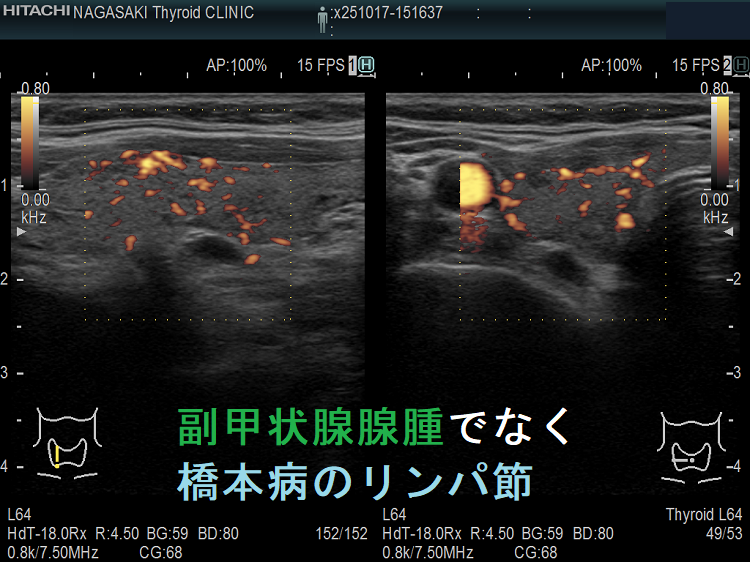

副甲状腺腺腫のように見えるも、実はただのリンパ節

副甲状腺腺腫との違いとして、リンパ節では

- 内部血流が無く

- リンパ門が存在します(ここだけ血流があります)

ケース①②